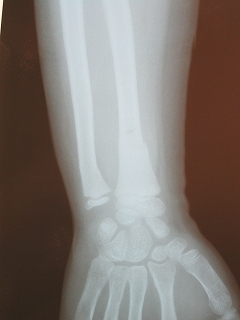

‰E‘O˜rœœÜ

@@”N—î@@8Î@—«

@@•‰“ú@•½¬14”N7ŒŽ27“ú

œÜÇ—á